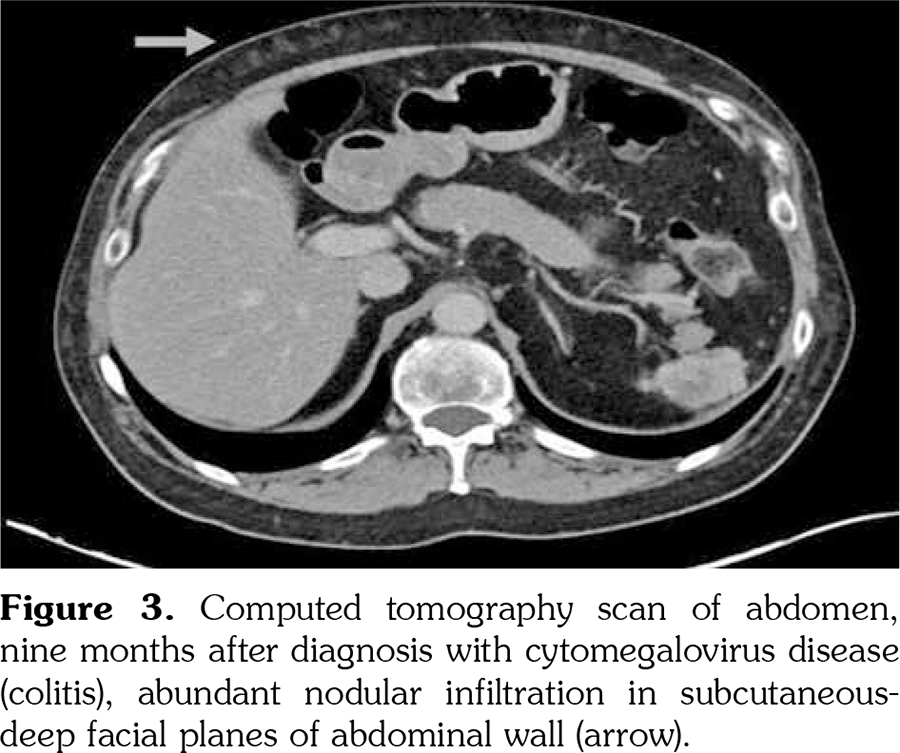

Eight months afterwards, he was hospitalized with a body temperature of 38.3°C and fatigue. On this admission, laboratory examinations revealed high C-reactive protein (4.76 mg/dL) level while no bacterial growth was observed in blood cultures. PCR test detected CMV DNA at 2,400 copies/mL. CT scan of the abdomen showed new abundant nodular infiltration in the subcutaneous-deep facial planes of the abdominal wall (Figure 3). Abdominal subcutaneous fat tissue true-cut biopsy was performed and CMV DNA was detected in the quantitative PCR assay of tissue specimen. He was put on oral valganciclovir treatment while mycophenolate mofetil was permanently discontinued. Following antiviral therapy, azathioprine was started and peripheral blood PCR assay revealed CMV DNA of 57 copies/mL at one month of this treatment.

Cutaneous CMV infection is a serious but rare condition because of the difficulties in diagnosis[11] In our case, discovering a recent nodular infiltration in the abdominal wall on CT scan and detecting CMV DNA at subcutaneous adipose tissue by PCR helped us to diagnose cutaneous CMV infection.